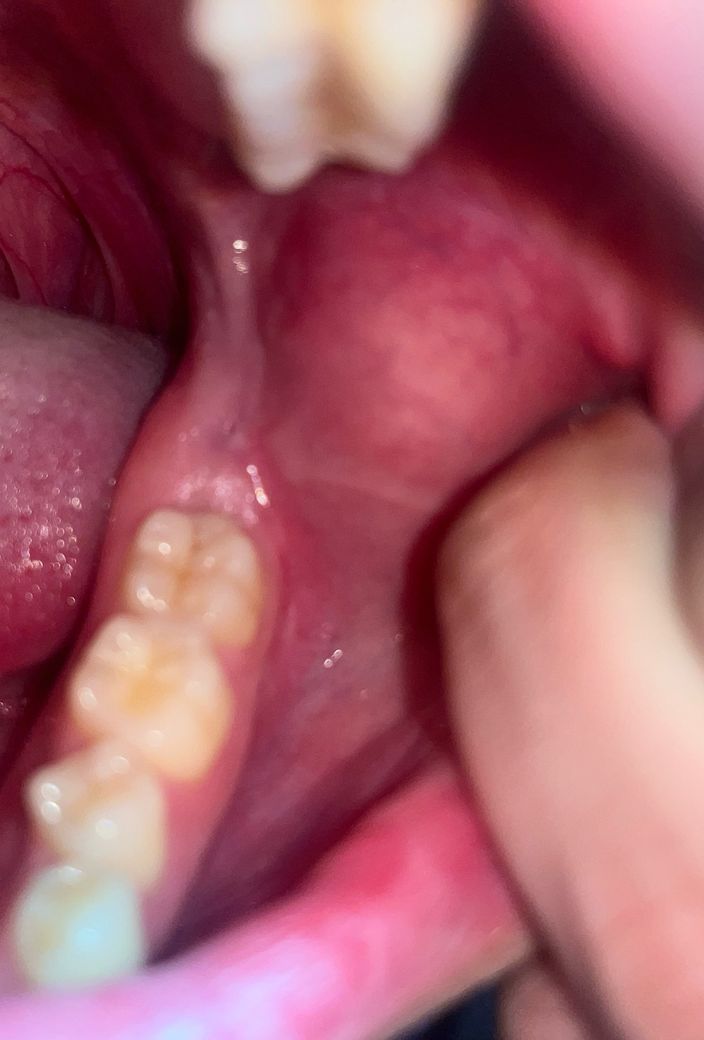

위에 사랑니가 있어서 아래 잇몸이 씹혀서 생긴 상처 인인가요? 아니면 구강암 증상인가요?

• 1번 째 사진

위의 사랑니로 인해 씹힌 자국인것 같습니다. 구강암 아닌것같고 구강암 되지는 않을것 같습니다. 치과에 내원하여 문제를 유발하는 사랑니 발치를 권장합니다. 빠른 쾌유 바라겠습니다. 건강하세요.

위에 사랑니가 있어서 그 부분이 계속 씹힌다면 사진처럼 상처와 자국이 생길 수 있습니다. 지금까지 밝혀진 구강암의 원인 중에 만성적인 자극이 있기는 하지만, 계속 사랑니에 씹히고 있는 상태에서 이것을 구강암이라고 보기는 어려우며, 구강암은 전체 암의 2프로도 채 되지 않으므로 확률도 희박하다고 볼 수 있습니다. 만약 사랑니를 발치해서 자극이 없어졌는데도 상처가 한달이상 낫지 않는다면 검사를 해보시는게 좋고, 구강암인지 알아보시려면 조직검사를 해봐야 합니다.